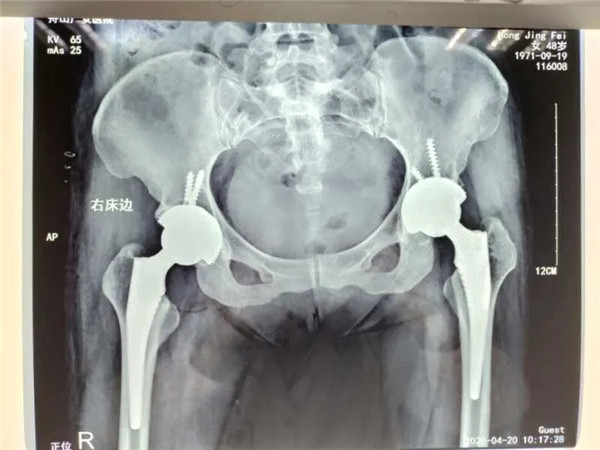

4月13日,危立軍副院長為洪女士實施了右側(cè)髖關節(jié)置換術,手術在關節(jié)鏡下完成,術后洪女士感覺良好。術后一周,洪女士便可以下地行走。目前,洪女士恢復良好,已經(jīng)出院回家休養(yǎng)。

雙側(cè)髖關節(jié)置換

值得一提的是,對于此次手術的人工關節(jié)材料,洪女士仍舊和三年前一樣,選擇了全陶瓷人工關節(jié)。